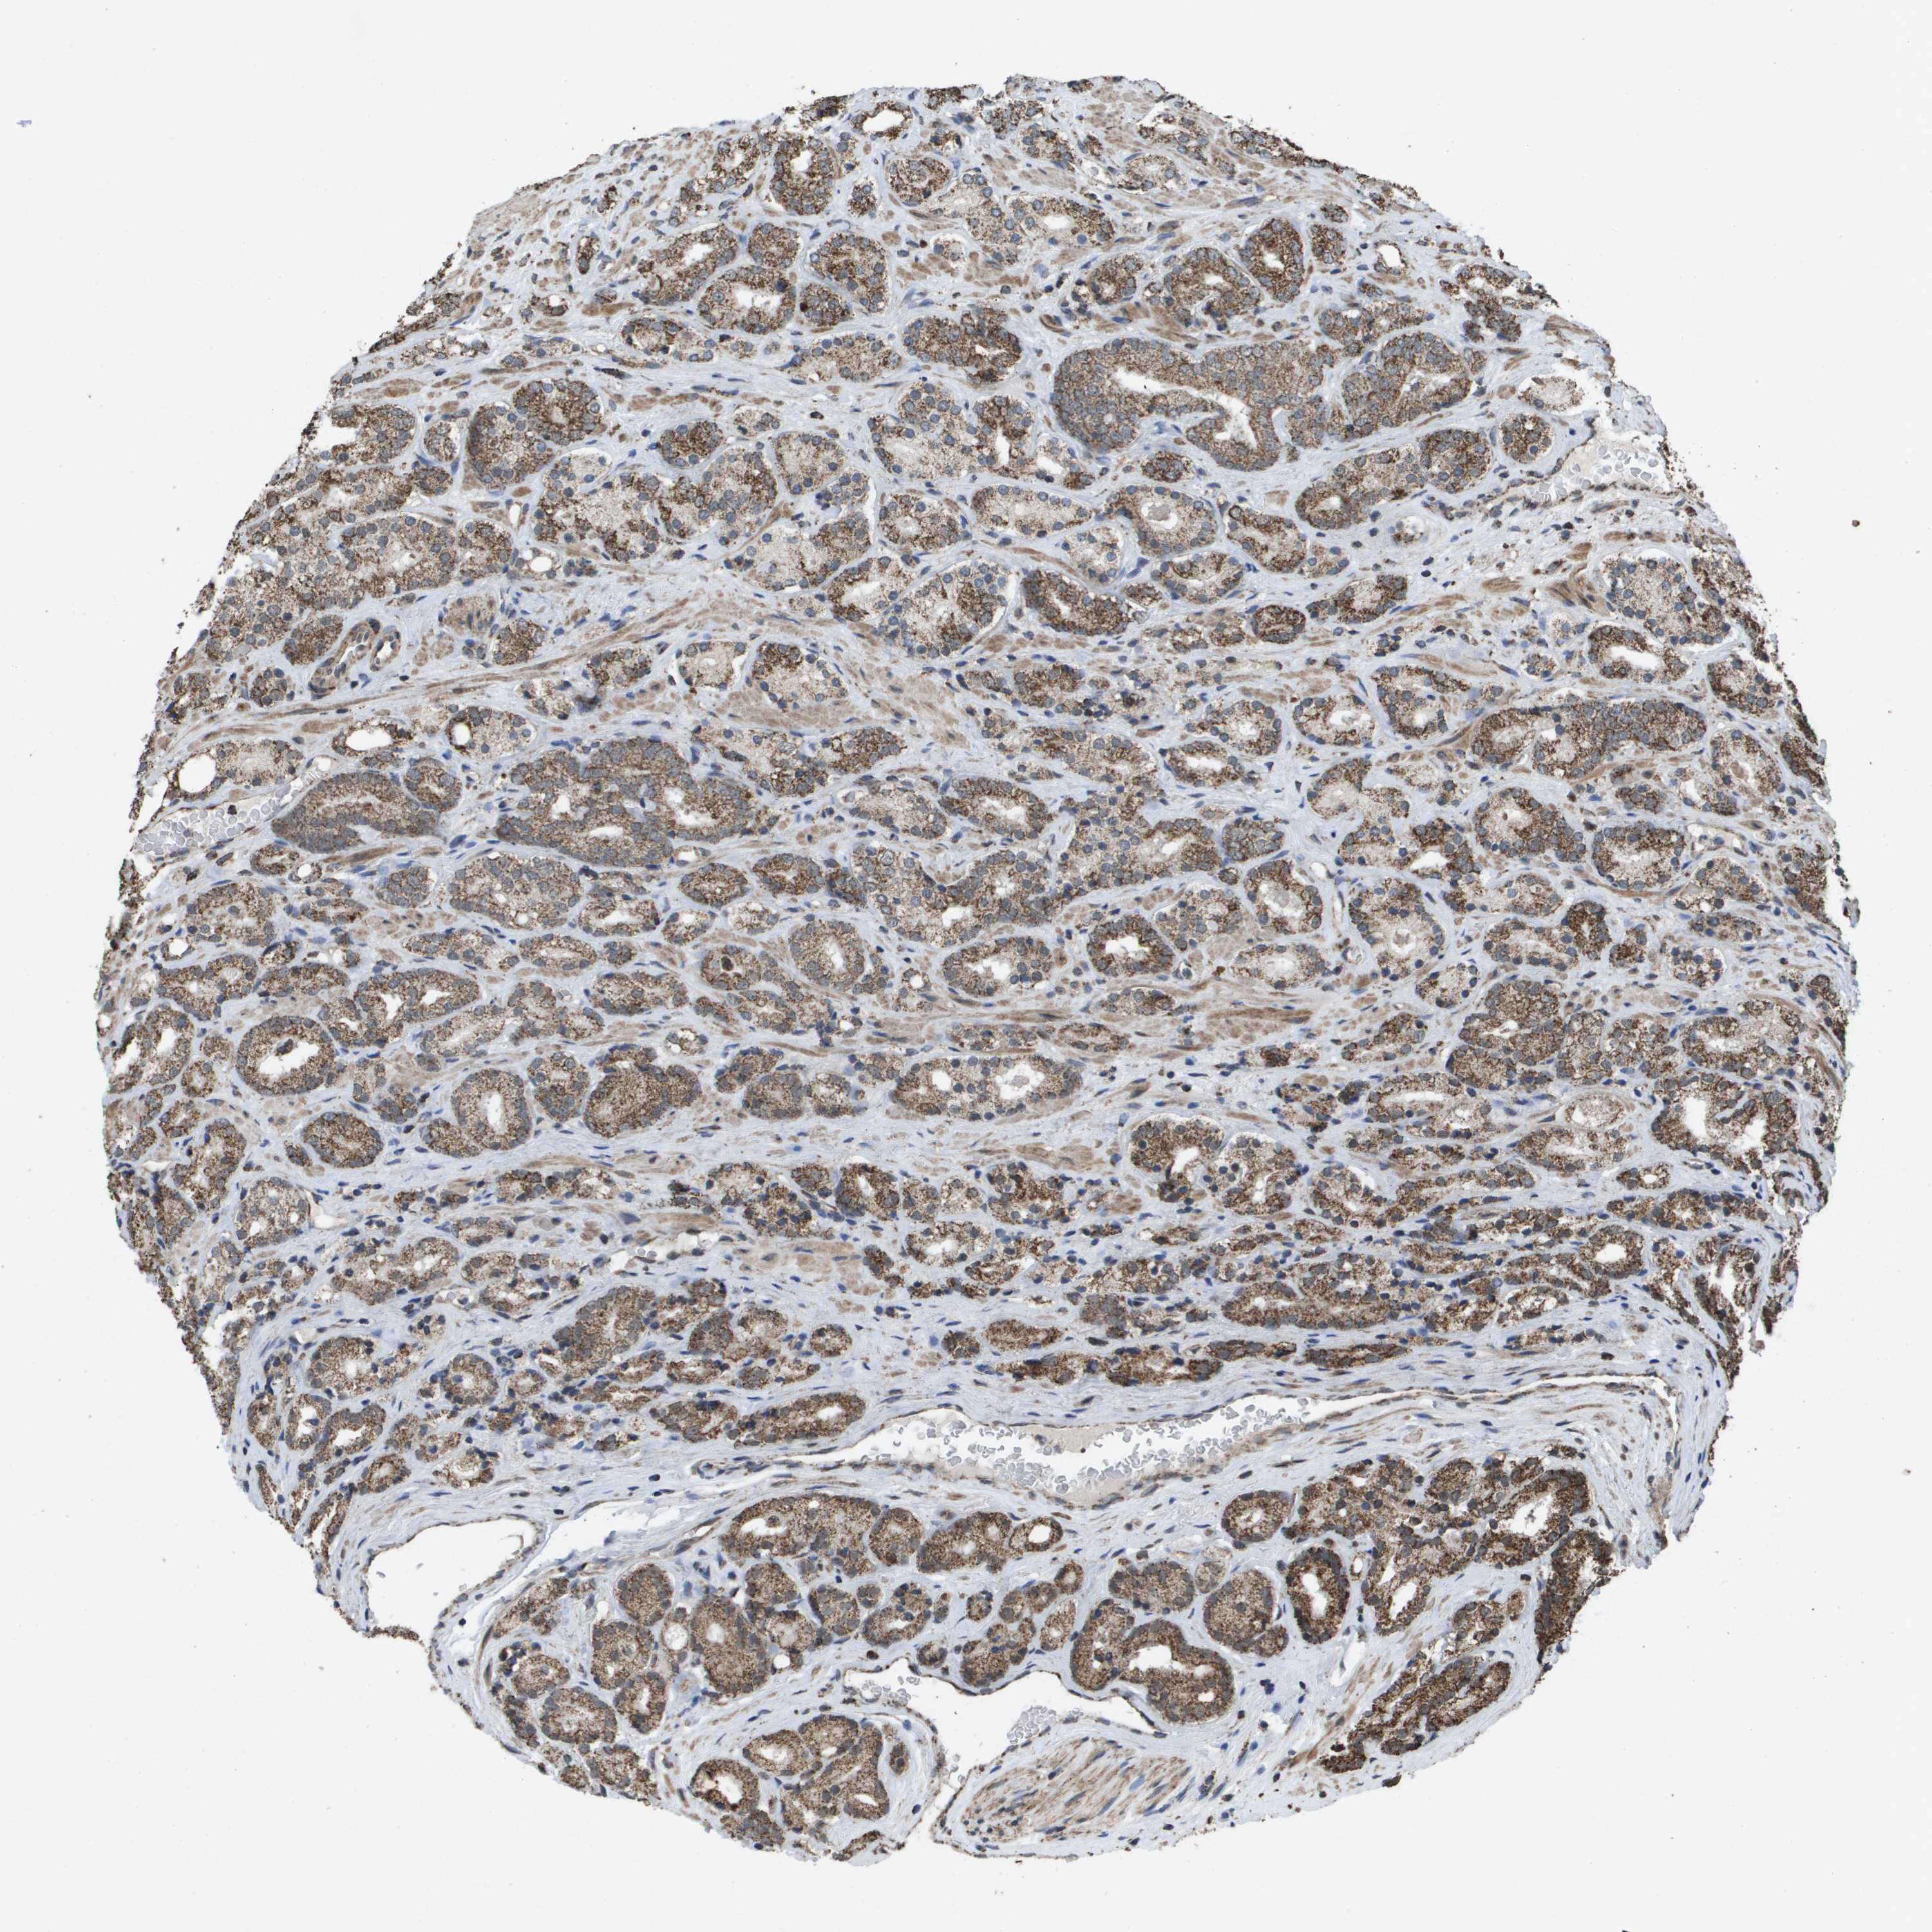

PROSTATE CANCER - Protein expressioni

A mouse-over function shows sample information and annotation data. Click on an image to view it in a full screen mode. Samples can be filtered based on level of antibody staining by selecting one or several of the following categories: high, medium, low and not detected. The assay and annotation is described here.

Note that samples used for immunohistochemistry by the Human Protein Atlas do not correspond to samples in the TCGA dataset.

Antibody stainingi

Antibody staining in the annotated cell types in the current human tissue is reported as not detected, low, medium, or high, based on conventional immunohistochemistry profiling in selected tissues. This score is based on the combination of the staining intensity and fraction of stained cells.

Each image is clickable and will lead to virtual microscopy that enables deeper exploration of all samples and also displays staining intensity scores, fraction scores and subcellular localization as well as patient and tissue information for each sample.

Antibody HPA038755

Antibody HPA048272

Antibody CAB017366

Staining

High

Medium

Low

Not detected

Intensity

Strong

Moderate

Weak

Negative

Quantity

>75%

75%-25%

<25%

None

Location

Nuclear

Cytoplasmic/membranous

Cytoplasmic/membranous,nuclear

Adenocarcinoma, NOS

Adenocarcinoma, High grade

Adenocarcinoma, Low grade